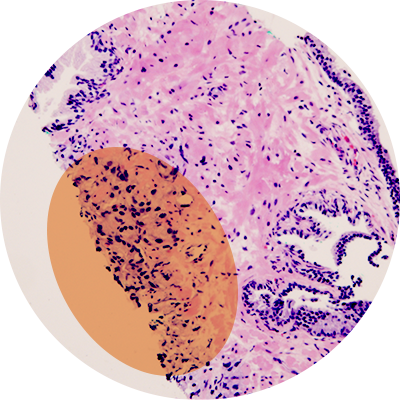

In a typical biopsy, a physician obtains a tissue sample and sends it to a laboratory for analysis. It may be chemically treated or frozen by a pathologist, then cut into sections to be examined under a microscope. Once the tissue has been altered for screening under the microscope, it can’t be tested for metabolites.

In a collaboration with the University of Alberta, Canada, researchers discovered that if the tissue is preserved in alcohol, instead of the more commonly used formalin, the preserving liquid also can be tested for metabolites.

The method is called molecular preservation by extraction and fixation (mPREF). In a proof-of-principle study, researchers used the method to study 25 samples from patients undergoing a prostatectomy. They found that 2,900 metabolites were consistently detected in more than 50 percent of the samples. This unprecedented coverage helped identify significant metabolites for differentiating tumor and normal tissues.